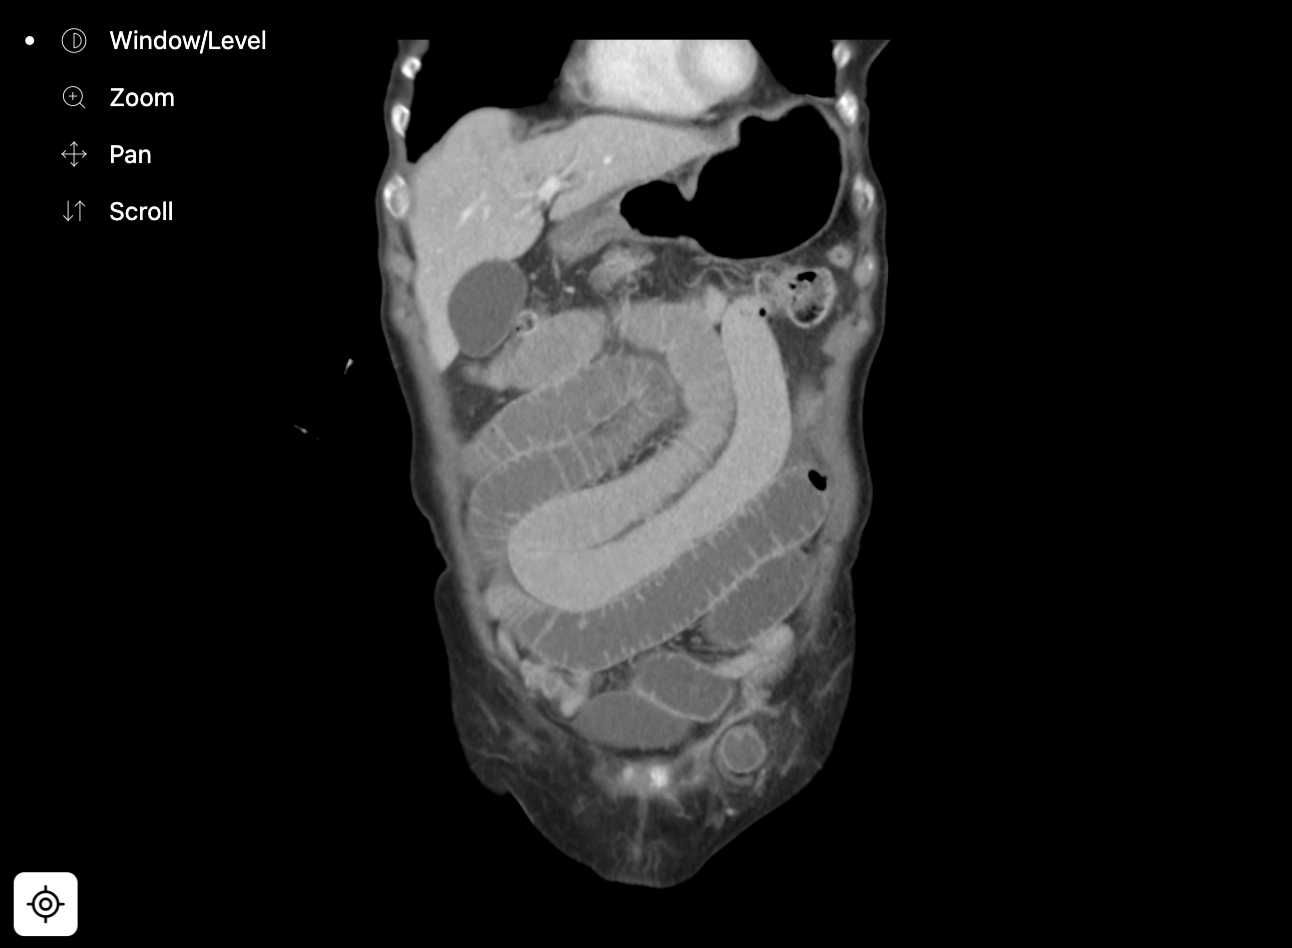

Small bowel obstruction due to a femoral hernia